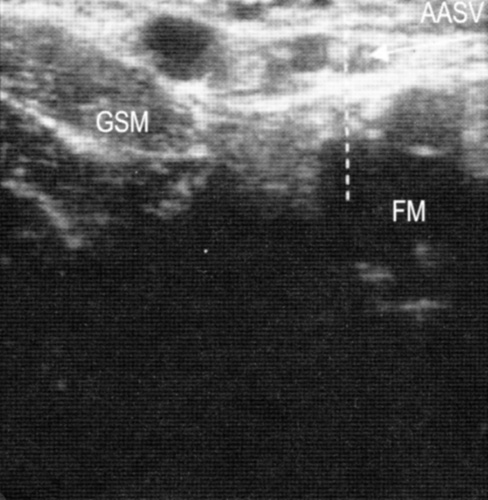

Симптом «строя». Большая подкожная вена и ее передний приток (передняя добавочная подкожная вена, ПДПВ) на поперечном срезе, сделанном на уровне верхней трети бедра, часто дают два симптома «глаза». В то же время ПДПВ лежит спереди и латерально по отношению к БПВ. При УЗДГ ее расположение меняется:она находится на одной линии над бедренной артерией и веной.

При УЗДГ в случае аплазии БПВ за симптом «глаза» «отвечает» ПДПВ, о чем можно судить по тому, что он (симптом) располагается над бедренной артерией и веной.

Симптом большеберцово-икроножного угла

Расположение большой подкожной вены относительно большеберцовой кости и камбаловидной мышцы позволяет при исследовании четко различать ее и подкожные притоки.

Диагностика варикоза

На поперечном ультразвуковом срезе большая подкожная вена в верхней трети голени располагается в треугольнике, образованном большеберцовой костью, камбаловидной мышцей и поверхностной фасцией. Это позволяет отличить большую подкожную вену от других вен, которые проходят рядом с ней. К сожалению, не всегда получается увидеть большую подкожную вену в верхней трети, поскольку листки фасции часто лежат совсем близко и закрывают фасциальный футляр.

Если же БПВ не находится в пределах данного фасциального футляра, это говорит о наличии у нее аплазии или гипоплазии.

Симптом малого подкожного пространства полезен для верной идентификации МПВ в верхней трети голени.